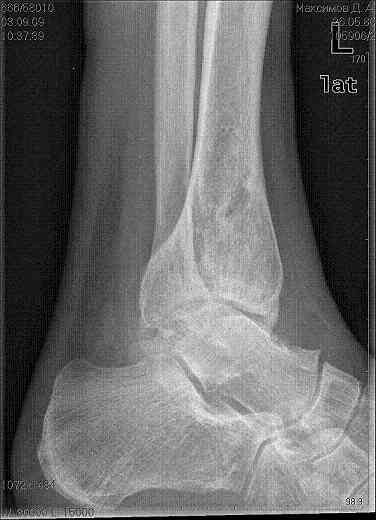

Здравствуйте коллеги. Представляю молодого человека 28 лет, получившего травму в апреле 2008года. Травму он получил на работе, левая голень со стопой оказались зажатыми между двумя тяжелыми предметами. В результате открытые переломы 1,2,3 плюсневых костей с размозжением мягких тканей над ними, открытый перелом наружной лодыжки со смещением дистального отломка кзади и подвывихом стопы кнаружи с размозжением мягких тканей над лодыжкой, закрытые переломы внутренней лодыжки и дистального метэпифиза большеберцовой кости.Учитывая наличие размозжения тканей стопы и области голеностопного сустава лечили в аппарате внешней фиксации. Переломы срослись, однако имеет место незначительный подвывих стопы кнаруже и неправильно сросшийся отломок наржной лодыжки (смещен кзади)Сегодня пациента ничего не беспокоит (с его слов. Клинически левый голеностопный сустав не отечный,пальпация всех структур данного сустава безболезненна. Имеет место ограничение тыльного сгибания стопы (сгибание к тылу стопы составляет до 10-15 гр), в связи с этим имеет место гиперподвижность в суставе Шопара. Пациент ходит со стельками (индивидуальные).Нужна ли пациенту реконструктивная операция в голеностопном суставе: исправление взаимоотношений в наружных отделах голеностопного сустава или что еще?С уважением Батал Шушания.

Наверное наружная лодыжка ушла назад не одна - такое впечатление, что был сломан и задний отдел б/берцовой кости (малоберцовая вроде прямая, а эпифиз широковат, как-то). Поэтому, думается, что гоняться за лодыжкой и синдесмозом не стоит. А вот вальгусный голеностоп и деф. артроз таранно-ладьевидного сустава - налицо. Вальгус надо устранять и, скорее всего, в АВФ единым блоком (надлодыжечная остеотомия обеих костей). Что пациент сам-то хочет? Если его устраивает нынешнее положение вещей, в стельках ему комфортно, то зачем огород городить (к этому суставу, рано или поздно, все-равно придется возвращаться)?

На рентгенограмме вальгус, на боковом снимке не видна суставная щель и клинически явная деформация.